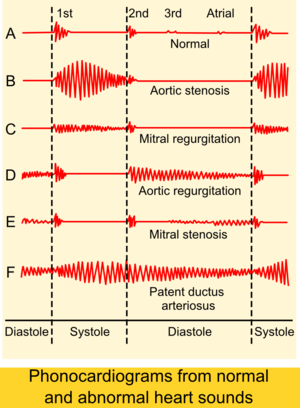

If there is increased stroke volume of the left ventricle due to volume overload, an ejection systolic 'flow' murmur may also be present when auscultating the same aortic area. Unless there is concomitant aortic valve stenosis, the murmur should not start with an ejection click.There may also be an Austin Flint murmur,[2] a soft mid-diastolic rumble heard at the apical area, it appears when regurgitant jet from the severe aortic insufficiency renders partial closure of the anterior mitral leaflet.Peripheral physical signs of aortic insufficiency are related to the high pulse pressure and the rapid decrease in blood pressure during diastole due to blood returning to the heart from the aorta through the incompetent aortic valve, although the usefulness of some of the eponymous signs has been questioned:[21] Phonocardiograms detect AI by having electric voltage mimic the sounds the heart makes.[22]